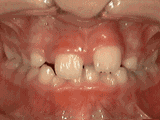

Phase I

Patient's parents were concerned about both aesthetics and the health of the erupting permanent teeth when they brought him to the orthodontist at age eight. The lower front teeth were crowded and they touched the palate, and the upper front teeth were extremely displaced from their normal positions. After twenty months of Phase I treatment with an expander and partial braces, patient's appearance and dental function was vastly improved.